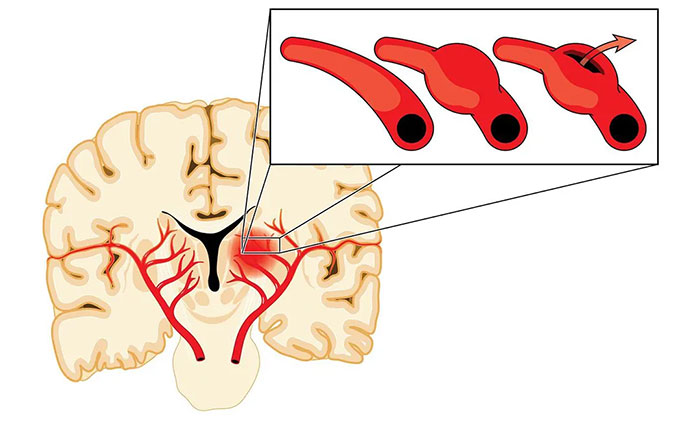

煙霧病的本質(zhì)是腦血管主干(頸內(nèi)動(dòng)脈和大腦中動(dòng)脈)的狹窄和閉塞,導(dǎo)致灌注異常,引起腦細(xì)胞缺血,同時(shí)又伴以代償性顱內(nèi)異常新生小血管。這些煙霧狀血管畢竟不是原始正常的血管,壁很薄,容易破裂出血,這就是煙霧病既容易引起腦梗死,又容易出血的原因。

手術(shù)則是目前最主要的煙霧病治療方式,可分為直接血運(yùn)重建術(shù)、間接血運(yùn)重建術(shù)以及聯(lián)合(直接+間接)血運(yùn)重建術(shù)。手術(shù)治療的目的,是使用來(lái)自頸外動(dòng)脈系統(tǒng)的血液供應(yīng)來(lái)增加顱內(nèi)血流,從而改善腦血流量和腦血流儲(chǔ)備能力。

“這就好比‘南水北調(diào)’,黃河水情不足時(shí),就從長(zhǎng)江引流,支援北地,緩解缺水局面。”宮衛(wèi)東主任形象地打了個(gè)比方,通過(guò)手術(shù)建立由腦外血管向腦內(nèi)供血的通路,改善腦內(nèi)血流。腦血供改善以后,對(duì)于煙霧狀血管的供血需求會(huì)逐漸減少,從而降低再次發(fā)生腦缺血和腦出血的風(fēng)險(xiǎn),改善患者的預(yù)后。